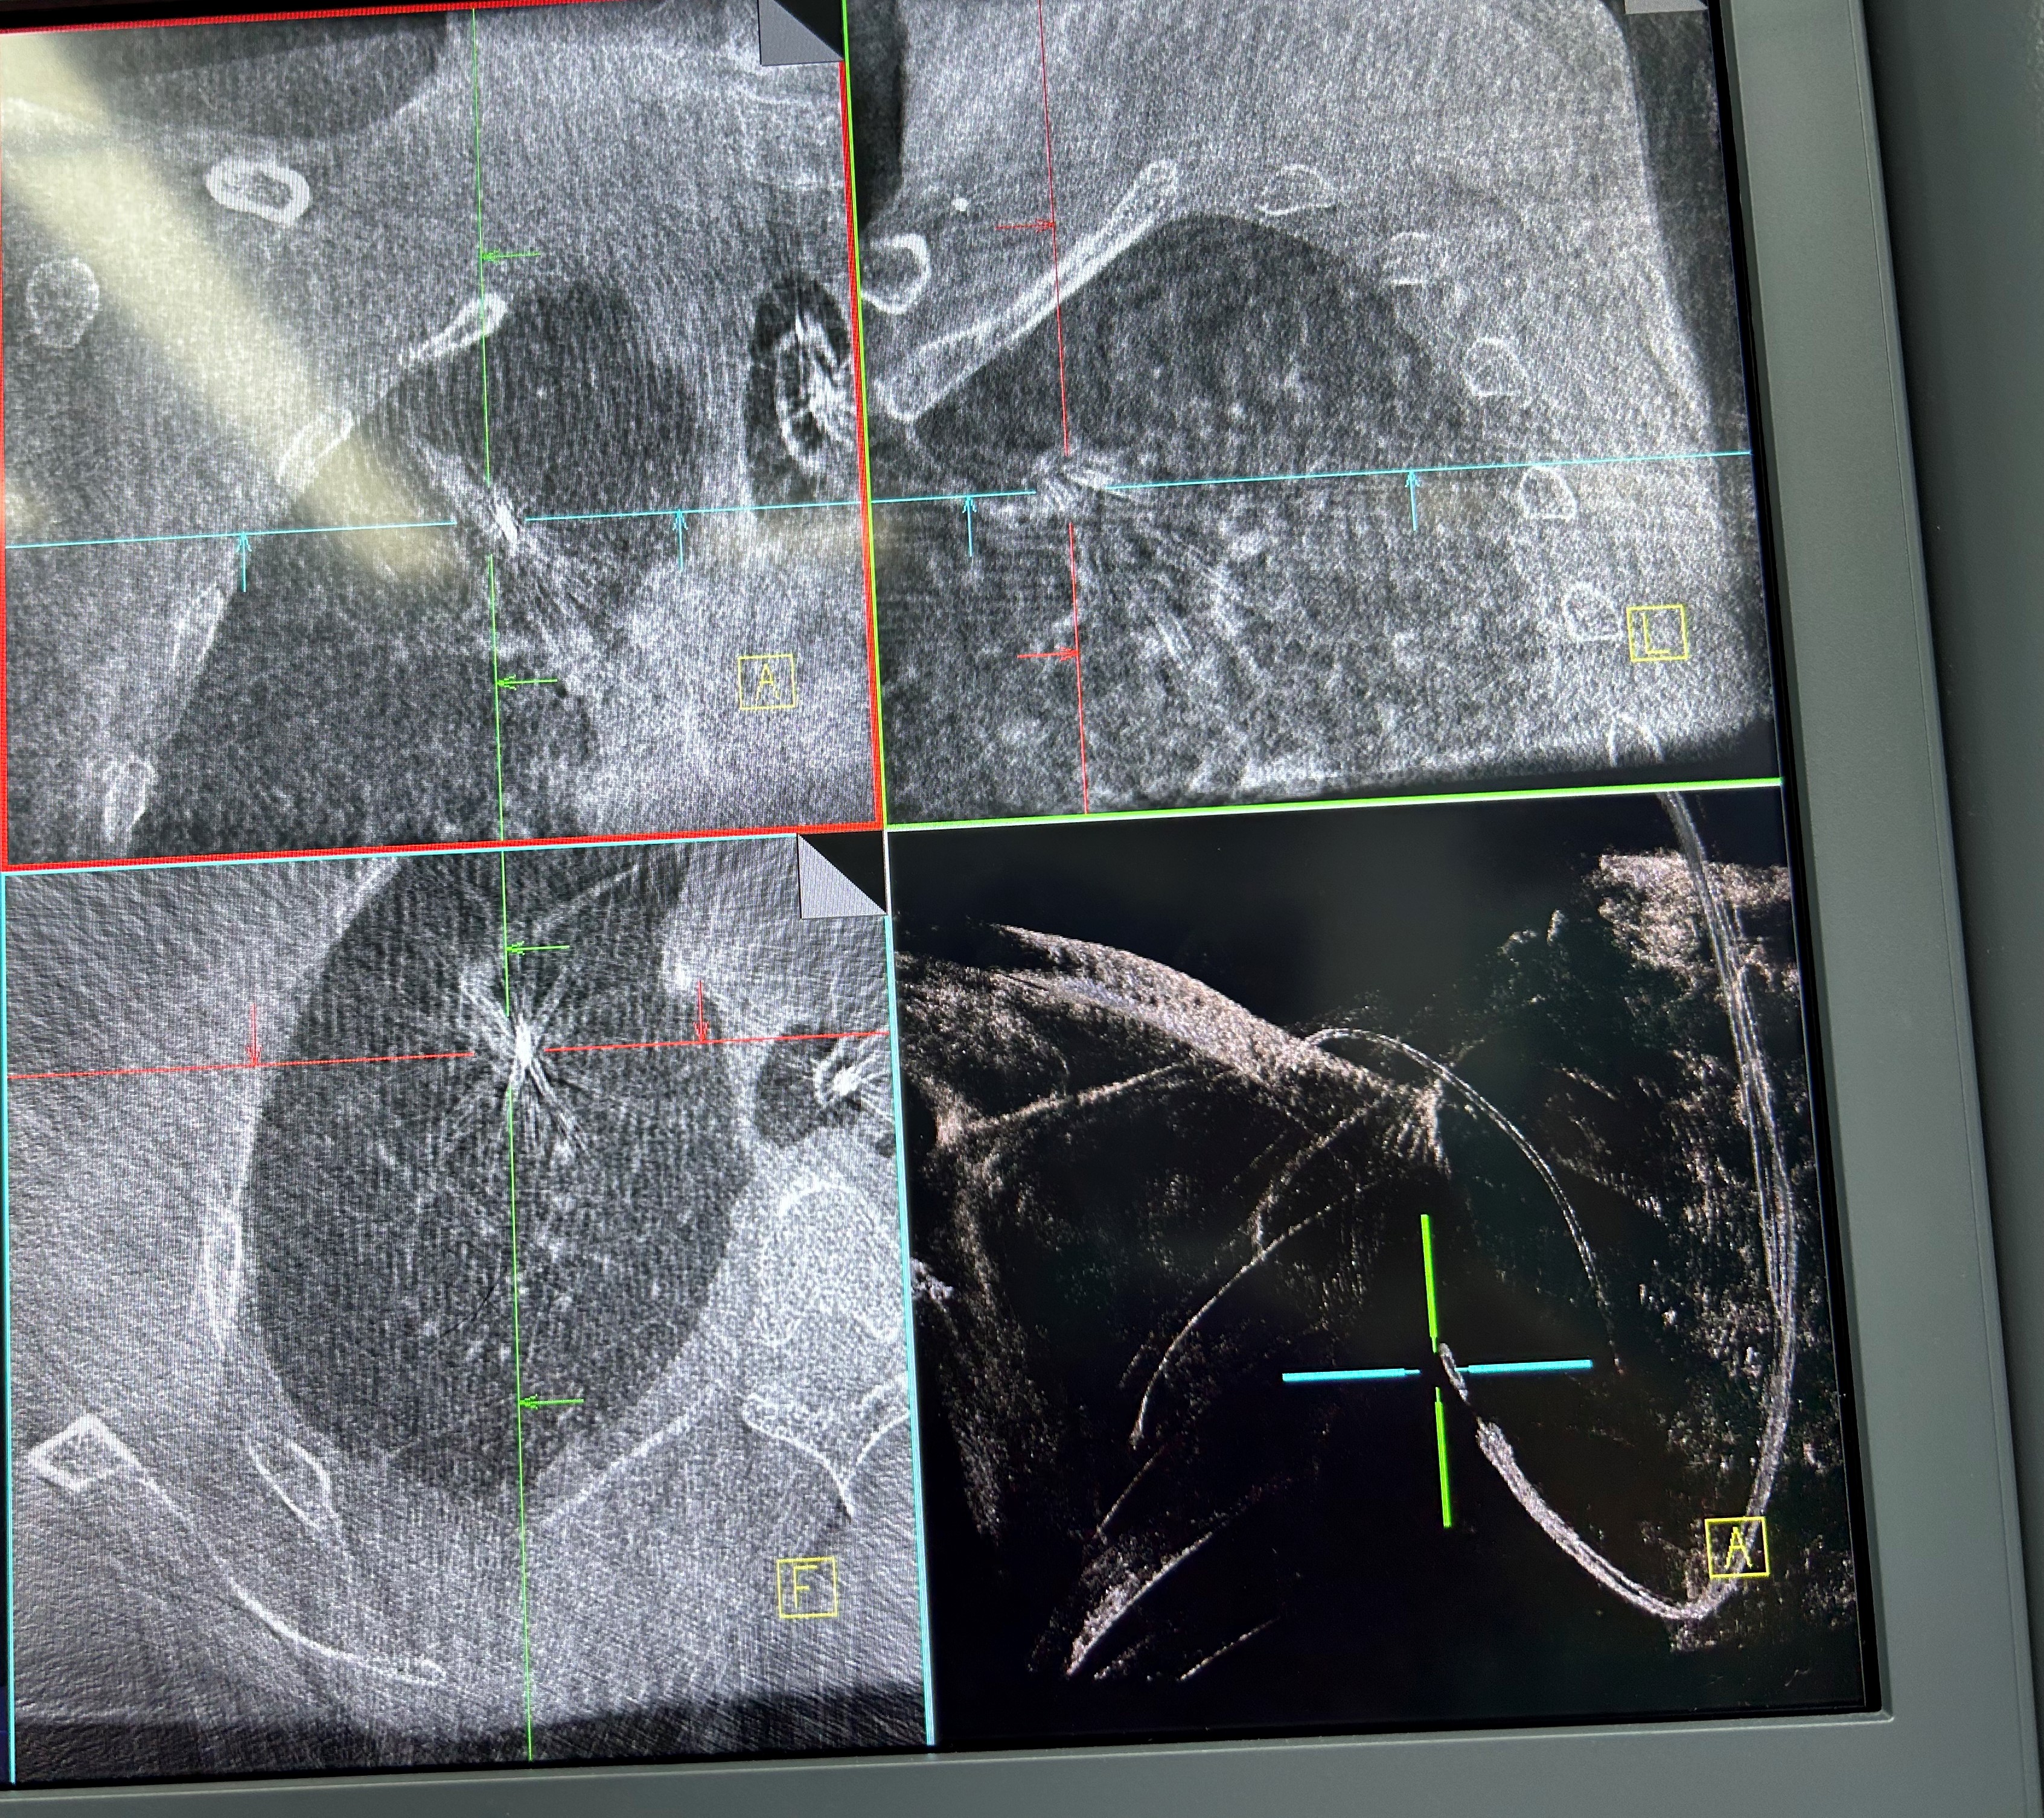

明确肿瘤诊断后,治疗方案即刻启动。团队经导航引导鞘管,精准插入一次性冷冻消融针(直径仅1.9mm)。再次通过CBCT确认消融针完全“扎根”于右上叶尖段病灶内后,开启冷冻治疗模式:以-160℃深低温冷冻10分钟、复温至45℃维持3分钟为一个治疗循环。完成了3次循环后,为确保病灶无遗漏,团队微调消融针位置,再次追加2次循环治疗。术后复查CBCT显示,病灶已呈现典型的冷冻后改变,术后两天复查胸部CT提示消融范围满意,治疗效果完全达到预期。整个手术过程中,患者生命体征始终平稳,术后第二天即可下床活动,真正实现了“微创治疗、快速恢复”的目标。

治疗后